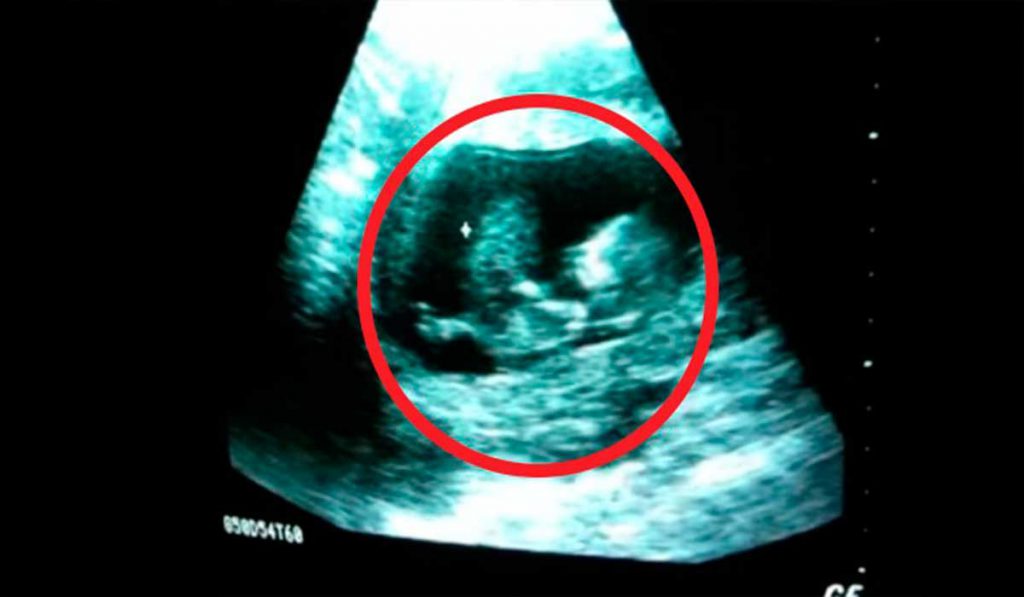

Cultura Ultrassom mostra quanto um bebê se diverte na barriga da mãe e revela o espetáculo da vida 1 de janeiro de 2016 editorialbow1 O que é mais belo do que ver uma pessoinha dentro de alguém prestes a vir ao mundo? Ah, a vida! O vídeo mostra um bebê brincando dentro da barriga da mãe e revela o espetáculo da vida!